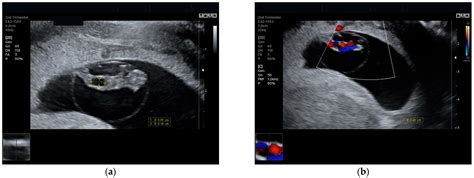

Diagnosis of an umbilical cord cyst is usually made through ultrasound imaging. During an ultrasound, the healthcare provider can visualize the cyst and assess its size, location, and any potential impact on the baby's health. In some cases, additional diagnostic tests, such as amniocentesis or fetal echocardiography, may be recommended to rule out other potential complications.